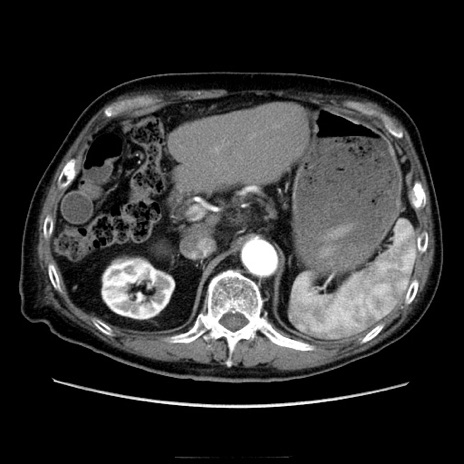

症例21(横断像)

【症例】70歳代男性

【主訴】腹痛

【現病歴】肝硬変・肝細胞癌にてかかりつけの方。約9時間前に食後より腹痛出現。症状が徐々に増悪し、嘔吐出現したため来院。

【既往歴】肝硬変、肝細胞癌(RFA、TACE後)

【身体所見】意識清明、表情苦悶様、BT 36℃、BP 129/78mmHg、P 88bpm、SpO2 97%(RA)、右上腹部から心窩部にかけて圧痛あり、反跳痛なし、筋性防御あり。

【データ】WBC 5800、CRP 0.16